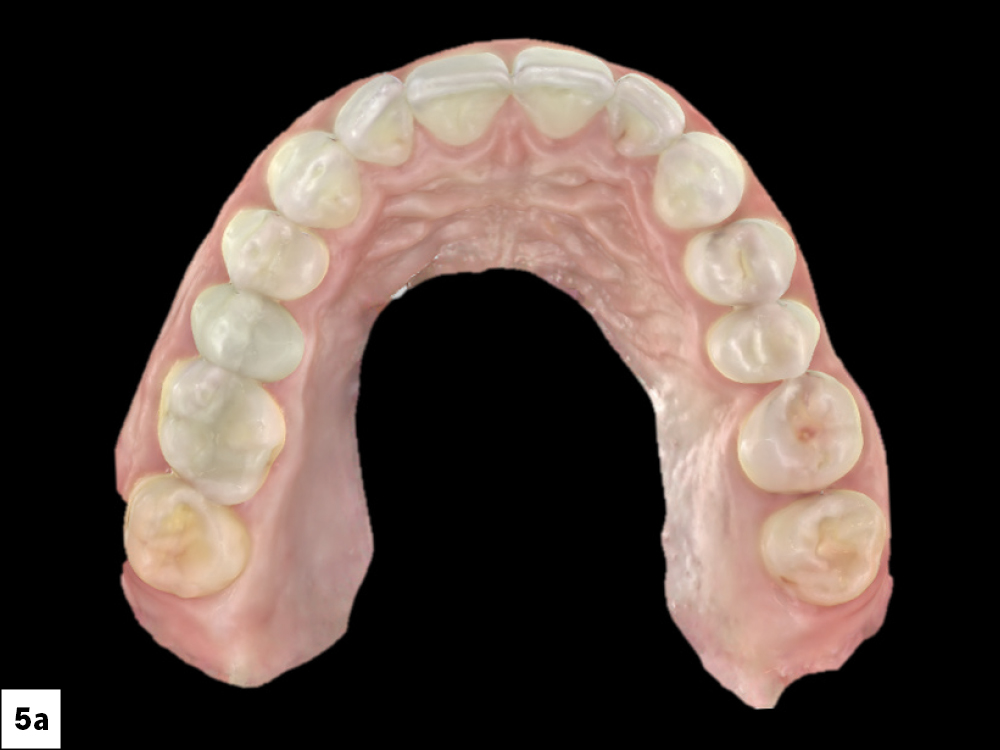

An intraoral scan of the patient’s mouth was taken using the fastscan.io™ Scanning Solution. This scan aids in visualizing the treatment plan and facilitates co-diagnosis with the patient. This same scan can then be used for implant planning and fabricating a surgical guide.

Figures 5a, 5b: An intraoral scan of the patient’s mouth was taken using the fastscan.io Scanning Solution. This scan aids in visualizing the treatment plan and facilitates co-diagnosis with the patient. This same scan can then be used for implant planning and fabricating a surgical guide.